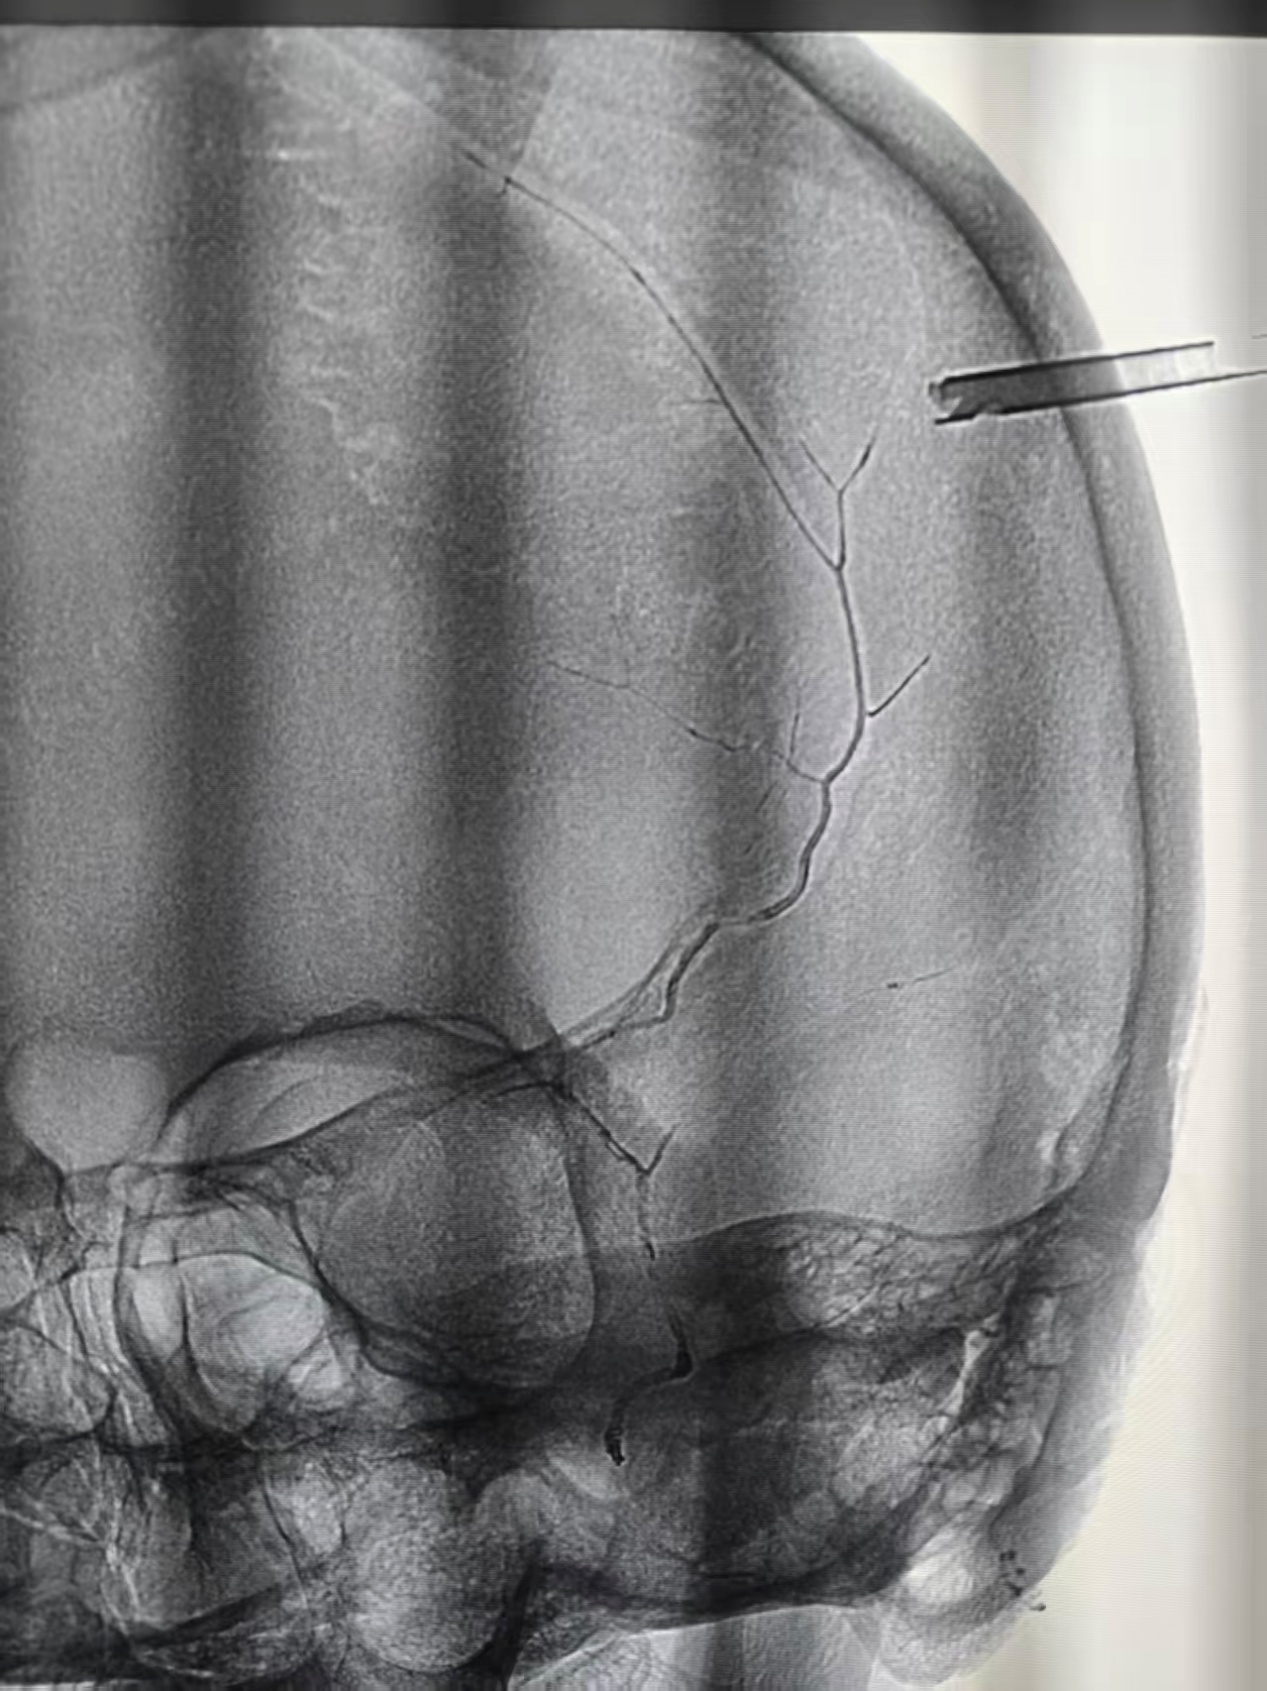

手术前,神经外科、麻醉科、护理团队提前做好各项准备,密切配合。手术时麻醉科医生精准调控麻醉深度,确保郑老伯生命体征稳定;神经外科医生先通过介入技术,在 DSA 设备引导下精准找到出血血管,用栓塞材料将其封堵,从源头上杜绝再出血可能;随后,团队迅速切换手术模式,采用微创方式打开颅骨,小心翼翼地清除颅内积压的血肿,解除脑组织压迫。整个手术过程紧张而有序,顺利完成。当医生告知家属 “手术非常成功,血肿已完全清除,出血血管也已封堵” 时,一直守在手术室外的家人终于松了一口气,悬着的心彻底放下。